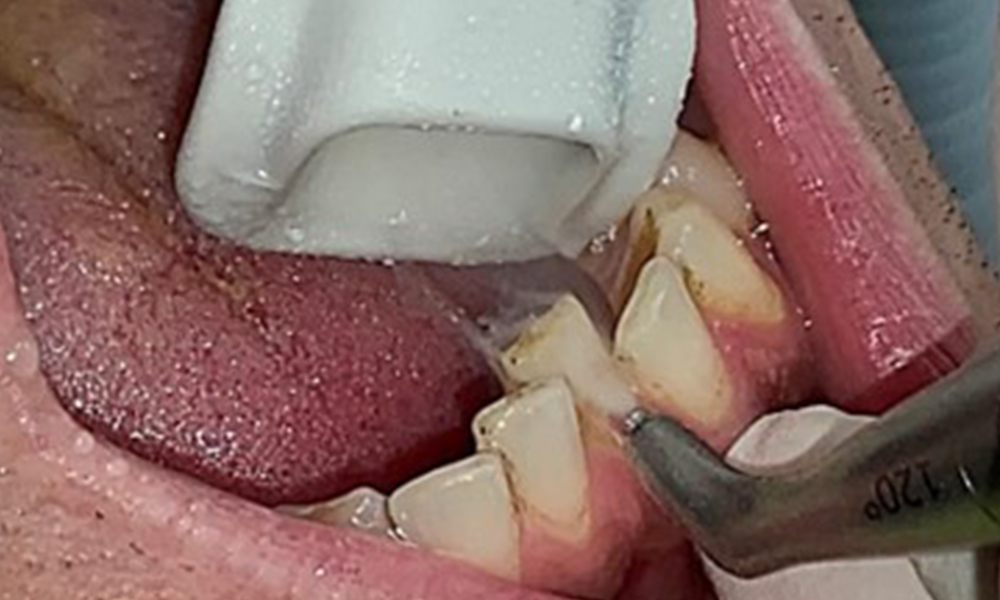

L'objectif serait de contrôler le risque de maladie en éliminant le biofilm supra-gingival et sous-gingival. Les instruments peuvent être sélectionnés en fonction des besoins du patient. Tout d'abord, le tartre et les concrétions doivent être éliminés à l'aide d'instruments ultrasoniques et/ou manuels (Fig. 10).